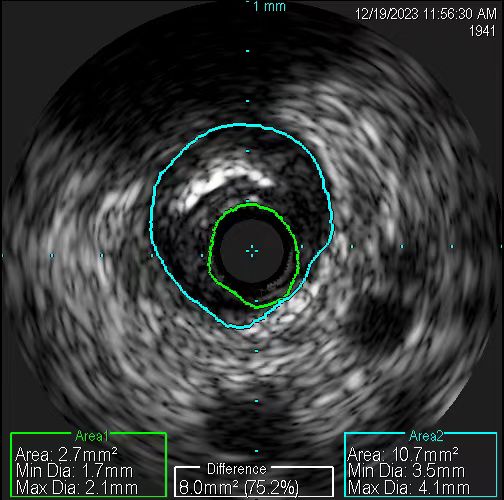

患者手術前的血管。

在無造影劑顯影情況下,冠脈導絲能否送達病變血管遠端,是手術的關鍵一步。操作稍有不慎,導絲就可能誤入分支,也可能穿出血管,引發致命后果。患者及家屬的充分信任,是手術得以進行的先決條件。12月19日11時許,在具備手術條件時,張慧晶帶領手術小組成員開始了挑戰。術前各項準備完成后,韓世飛在李占虎協助下將指引導管順利放置于右冠開口,他依據豐富的手術經驗,將導絲成功送入到右冠遠端,血管內超聲(IVUS)探頭順利到位后便開始進行精準的檢查。結果提示:患者右冠原支架貼壁良好、膨脹充分,進一步證實了此次犯病不是源于右冠。再行前降支IVUS檢查,依靠上次冠脈造影圖像作為參照,指引導管、主支導絲順利到位,反復多次進行IVUS檢查。張宏博根據IVUS圖像及時進行精準的測量,前降支近段最小管腔面積2.7mm2,中段斑塊負荷重,均達到處理標準;遠段血管直徑約2.5mm,近段血管直徑約3mm。張慧晶帶領大家根據IVUS檢查結果,制定了詳盡的支架植入方案:應用血管內超聲的換能器精準測量,輔以分支導絲做為路標,一舉將支架成功釋放到理想位置。最終經IVUS檢查提示:支架膨脹充分、貼壁良好,無殘余狹窄及邊緣夾層。歷時近2小時,手術過程順利,全程未使用一滴造影劑,患者未出現任何不適及并發癥。術后復查心臟超聲較前無變化,無心包積液,確定了無穿孔發生。